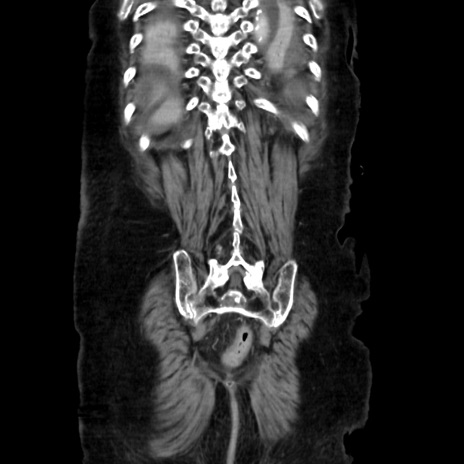

症例40(冠状断像)

【症例】90歳代女性

【主訴】腹痛・嘔吐

【現病歴】 食欲低下、嘔吐があり昨日他院受診。肺炎と診断され入院となる。入院後より腹部全体に圧痛あり。胃管留置され経過みていたが、症状持続するため、

当院転院となる。

【既往歴】胸椎圧迫骨折、胆石症

【身体所見】腹部:中央に激痛あり、圧痛あり、反跳痛不明

【データ】WBC 17100、CRP 18.82

矢状断像